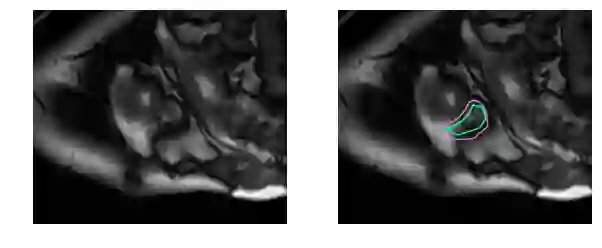

而这对于没有经过训练的眼睛来说完全是一个挑战:

事实上,与左心室相比,医生需要耗费两倍的时间来确定右心室的体积并生成结果。这项工作的目的是建立一个高度准确的右心室自动分割深度学习模型。模型的输出是*分割掩码*,即一个逐像素的掩码,用来表示某个像素是否是右心室的一部分或只是背景。